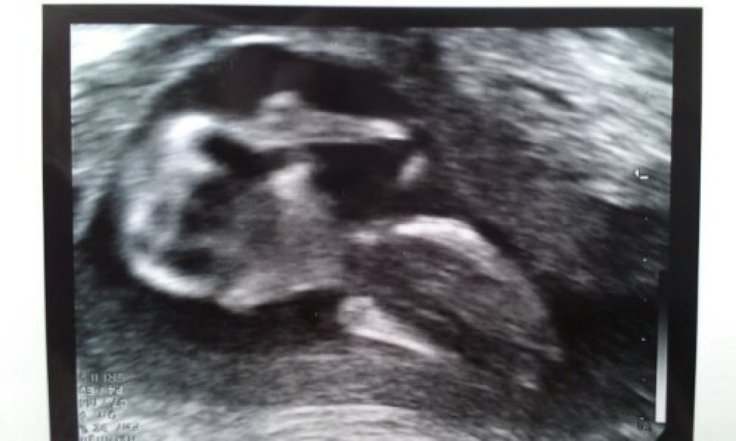

Idag var jag på ännu ett ultraljud. Ett så kallat notchultraljud för att kolla att mina flöden är bra och att tillväxten på bebisen är som den ska. Jag kommer minsann bli granskad utan och innan den här gången och hinna se bebisen på skärmen många gånger innan den, hon, tittar ut. Så blir det tydligen om man haft havandeskapsförgiftning förut.

Jag, eller vi, måste nog också börja vänja oss vid att kalla bebisen för hon för barnmorskorna hittar, inte ens en liten snopp, när de letar.